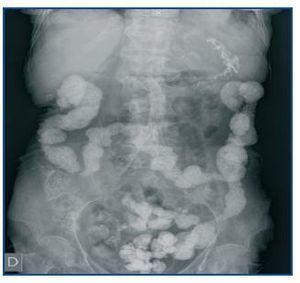

El carbonato de lantano es un quelante del fósforo, libre de calcio y aluminio, de reciente comercialización en España. Se trata de un metal pesado con nula absorción intestinal que no presenta toxicidad. En la ficha técnica del producto en nuestro país, no se cita el fenómeno de aparición de imágenes radiológicas. No ocurre así en la versión americana, donde se advierte que «pueden aparecer imágenes radioopacas en la radiografía abdominal en pacientes consumidores de lantano»1. Las reacciones adversas notificadas con mayor frecuencia fueron gastrointestinales, pero en los ensayos clínicos no se incluyeron pacientes con obstrucción intestinal ni enfermedad inflamatoria intestinal2. Presentamos el caso de un hombre de 58 años, con diverticulosis pancolónica y frecuentes episodios de diverticulitis, con ERC secundaria a nefropatía diabética e inicio de programa de hemodiálisis periódica en abril de 2001. Ingresa en julio de 2008 por fiebre y dolor abdominal. Se realiza una TAC abdominal urgente que descarta signos de diverticulitis, pero es informado por el radiólogo como «restos de contraste en todo el colon e íleon terminal» (figura 1), imagen confirmada en una radiografía simple de abdomen (figura 2). Nuestro paciente no había recibido contraste radiológico en ningún momento, pero estaba siendo tratado con 3.000 mg diarios de carbonato de lantano desde febrero de este año por hiperfosforemia grave, con excelentes resultados analíticos y buena tolerancia clínica hasta el momento. El diagnóstico final fue de sepsis por Enterococo avium, de probable origen intestinal. Dado que no se encontraron otros hallazgos en las pruebas de imagen que justificaran el dolor abdominal, se suspendió el tratamiento con lantano, permaneciendo posteriormente asintomático.

Figura 1. TAC abdominal sin contraste que muestra depósito de carbonato de lantano en los divertículos del colon sigmoides y en recto.